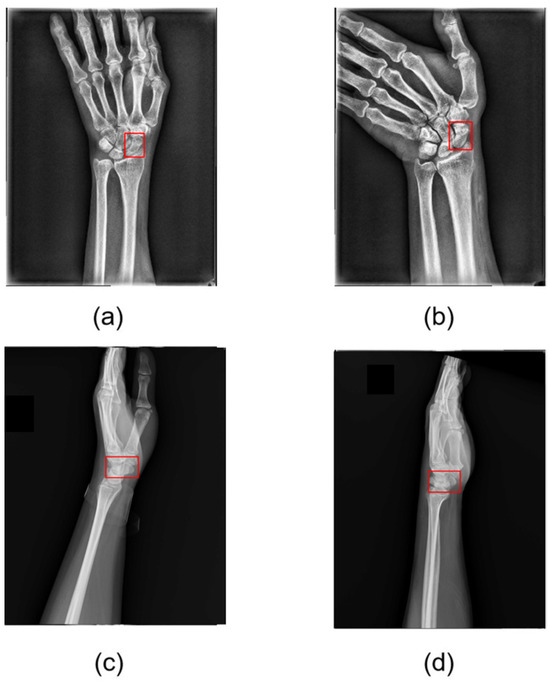

Scaphoid Fracture Detection and Localization Using Denoising Diffusion Models

Background/Objectives: Scaphoid fractures are a common wrist injury, typically diagnosed and treated through X-ray imaging, a process that is often time-consuming. Among the various types of scaphoid fractures, occult and nondisplaced fractures pose significant diagnostic challenges due to their subtle appearance and variable [...] Read more.

Background/Objectives: Scaphoid fractures are a common wrist injury, typically diagnosed and treated through X-ray imaging, a process that is often time-consuming. Among the various types of scaphoid fractures, occult and nondisplaced fractures pose significant diagnostic challenges due to their subtle appearance and variable bone density, complicating accurate identification via X-ray images. Therefore, creating a reliable assist diagnostic system based on deep learning for the scaphoid fracture detection and localization is critical. Methods: This study proposes a scaphoid fracture detection and localization framework based on diffusion models. In Stage I, we augment the training data set by embedding fracture anomalies. Pseudofracture regions are generated on healthy scaphoid images, producing healthy and fractured data sets, forming a self-supervised learning strategy that avoids the complex and time-consuming manual annotation of medical images. In Stage II, a diffusion-based reconstruction model learns the features of healthy scaphoid images to perform high-quality reconstruction of pseudofractured scaphoid images, generating healthy scaphoid images. In Stage III, a U-Net-like network identifies differences between the target and reconstructed images, using these differences to determine whether the target scaphoid image contains a fracture. Results: After model training, we evaluated its diagnostic performance on real scaphoid images by comparing the model’s results with precise fracture locations further annotated by physicians. The proposed method achieved an image area under the receiver operating characteristic curve (AUROC) of 0.993 for scaphoid fracture detection, corresponding to an accuracy of 0.983, recall of 1.00, and precision of 0.975. For fracture localization, the model achieved a pixel AUROC of 0.978 and a pixel region overlap of 0.921. Conclusions: This study shows promise as a reliable, powerful, and scalable solution for the scaphoid fracture detection and localization. Experimental results demonstrate the strong performance of the denoising diffusion models; these models can significantly reduce diagnostic time while precisely localizing potential fracture regions, identifying conditions overlooked by the human eye. Full article

Show Figures

Figure 1